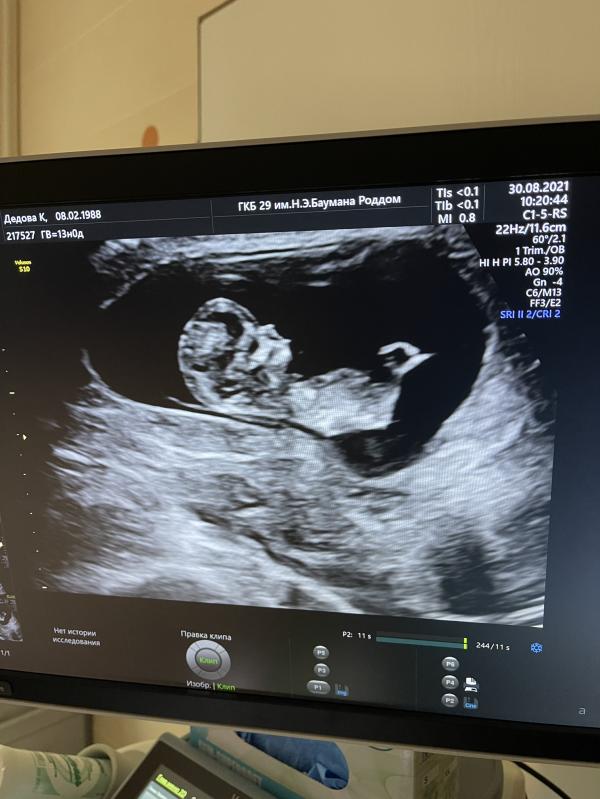

Была сегодня на первом скрининге 😻 Вот вроде уже третий ребёнок, а все равно какой-то детский восторг)) Предположили девочку, что сходится с результатом анализа по крови)) Теперь еле сдерживаю себя, чтобы не начать скупать малышковые вещички))

29 роддом... Знакомые места, рожала там свою дочку, надеюсь вернусь туда в апреле💕💕